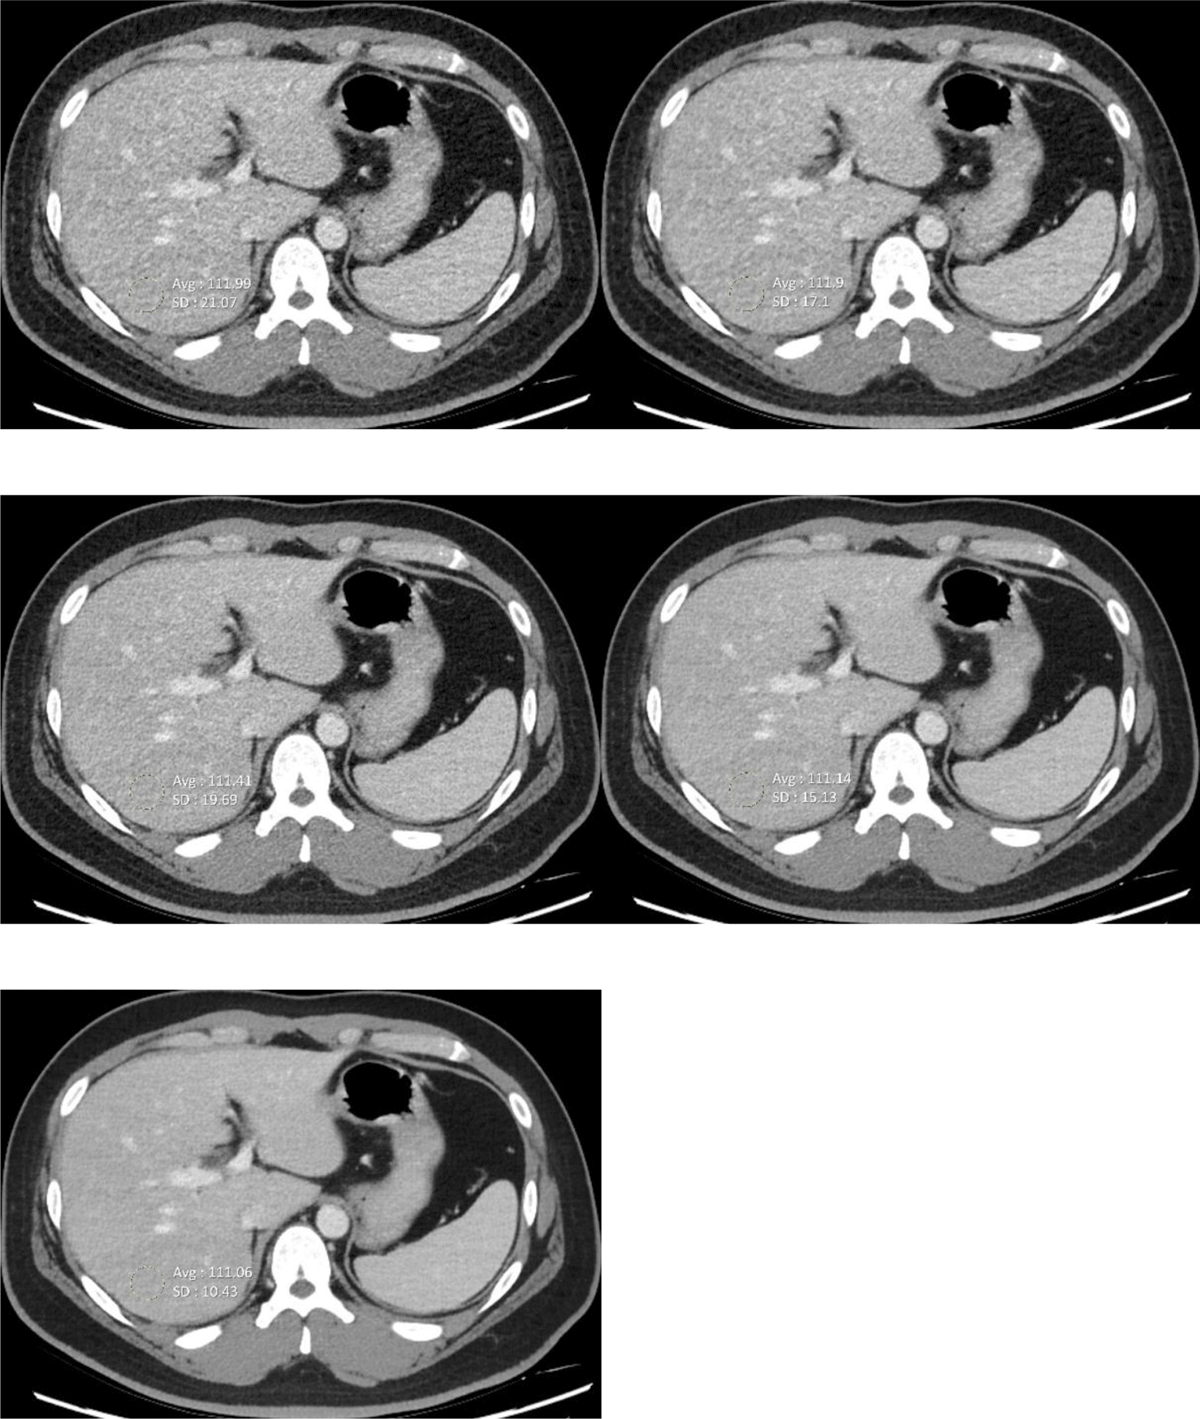

Figure 2

CT images for quantitative analysis of liver (a) AV 30 (b) AV 50 (c) DLIR-L (d) DLIR-M (e) DLIR-H. The body mass index of this patient is 34.3.

FBP, filtered back projection; AV, adaptive statistical iterative reconstruction; DLIR, deep learning-based image reconstruction; DLIR-L, DLIR images with low levels; DLIR-M, DLIR with medium levels.